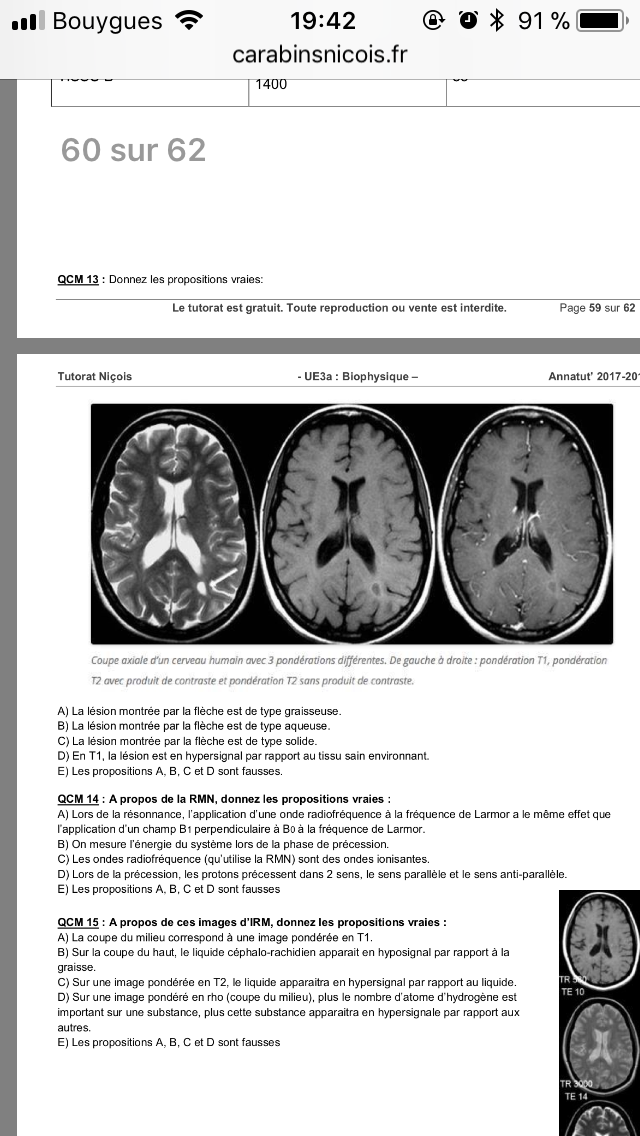

Ensuite pour le qcms 11 on est d’acord que si TR est court forcement c’est T1 quelque sois le TE donc on aurait pu choisir A et B

Et enfin.qcm 15 Pour l’item B c’est faux mais sur l’image c’est ecrti TR grand et TE court donc —> rho hors en rho on sais que l’eau apparait en hypersignal or dans l’item c’est dit « hyposignal » ..